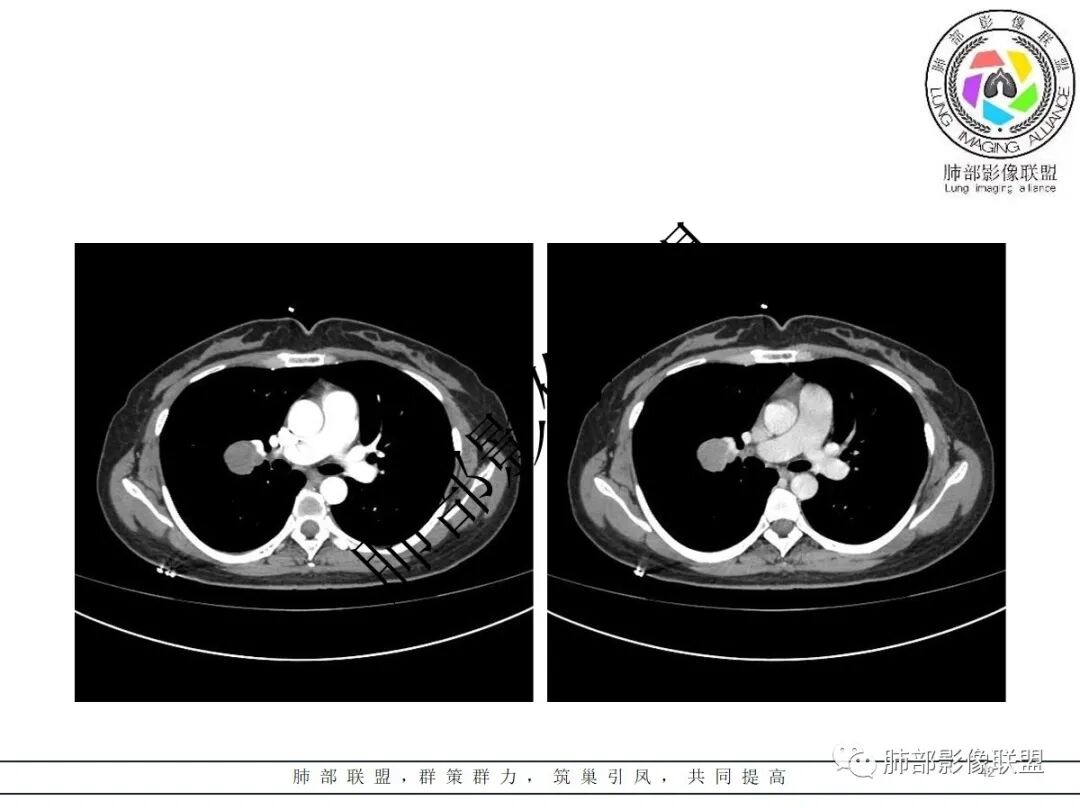

右肺门类圆形实性肿块,边缘光滑,无分叶毛刺,跨叶,推移血管,密度均匀,增强延迟强化相对明显,未见坏死及血管造影征。

右肺门区类圆形肿块,跨叶,边缘光滑,密度均匀,血管贴边,推移,延迟强化,考虑PSP,鉴别CD

2.右肺水平叶裂斜叶裂肺门交界区类椭圆形块影,表面光整,未见分叶毛刺及棘状突起,未见邻近结构牵拉。与邻近支气管无关联。

3.病灶密度均匀,未见液化坏死、钙化及脂肪低密度。轻度强化,可见纤细血管影蜿蜒穿行。右肺动脉推移变形,未见侵入或充盈缺损。

4.灶周未见磨玻璃晕或极低密度影环绕。右肺下叶背段胸膜下见微小实性密度结节影,边界清楚。

5.双肺门及纵隔未见增大淋巴结。双侧胸腔未见积液。